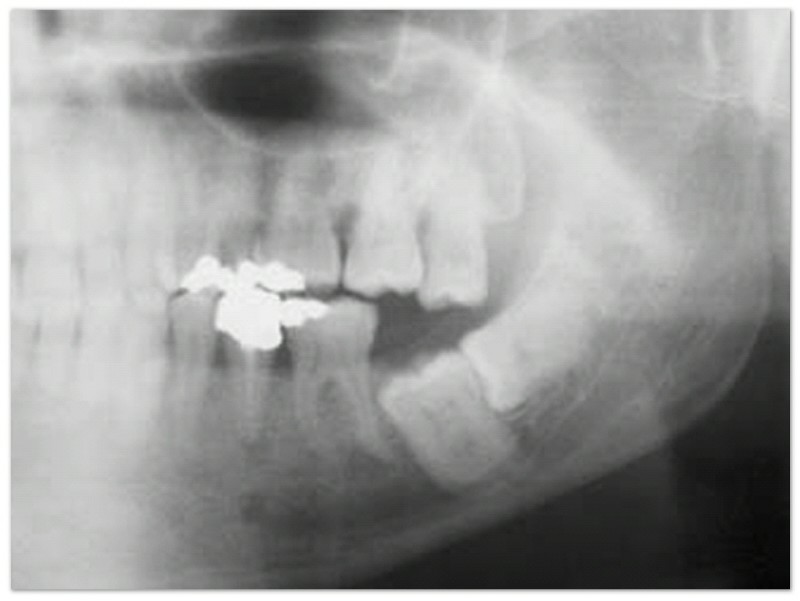

Gigi bungsu sering tumbuh dengan arah miring ke depan, sehingga mendorong gigi-gigi di depannya dan membuat gigi di depannya menjadi berantakan. Oleh karena itu, apabila ingin menggunakan kawat gigi, dokter gigi sering menganjurkan pengambilan gigi bungsu yang menjadi penyebab gigi berantakan.

Merusak akar gigi sebelahnya.

Selain menyebabkan gigi berantakan, gigi bungsu yang arah tumbuhnya ke depan juga dapat menyebabkan gigi di sebelahnya menjadi rusak.